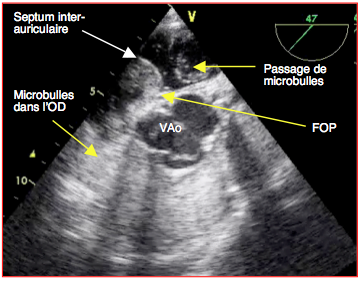

Le test aux microbulles consiste à injecter 10 mL de NaCl 0.9% dans lesquels on a préalablement provoqué une cavitation en faisant faire des allers-retours au liquide entre deux seringues reliées par un robinet 3-voies (Figure 27.155B). L’injection se fait rapidement, si possible par une voie centrale. Le test comprend 2 phases [32,33].

Figure 27.155B : Test aux microbulles lors de FOP. Dès leur arrivée dans l’OD, de nombreuses microbulles passent dans l’OG lorsque la postcharge du VD augmente (manoeuvre de Valsalva, PEEP) ou lorsque le volume de l’OD est supérieur à celui de l’OG (manoeuvre de Mueller, déconnexion respiratoire) [11,12].

Pour que l'élévation de la POD soit certaine, le septum doit bomber dans l'OG [27]. Les microbulles apparaissent immédiatement dans l’OG (Vidéo); si elles n’arrivent que 3-5 cycles cardiaques plus tard, elles sont le fruit d’un passage transpulmonaire. Pour bien les voir, il est recommandé de visualiser la partie haute de l’OG ansi que la CCVG ou la racine de l’aorte (pour contrôler leur passage). Le test est positif si > 5 bulles sont visibles rapidement dans l’OG; il est fortement positif si l'on compte > 25 microbulles. La présence d’un flux couleur signale l’existence d’un shunt G→D, et celle de microbulles dans l’OD la possibilité d’un shunt D→G. Il se peut parfaitement que le test aux microbulles soit négatif alors que le flux couleur indique la présence d’un FOP si la POG reste largement supérieure à la POD en permanence (insuffisance ventriculaire gauche, sténose mitrale) et que les manœuvres de provocation ne parviennent pas à renverser cet équilibre [1,2,31].